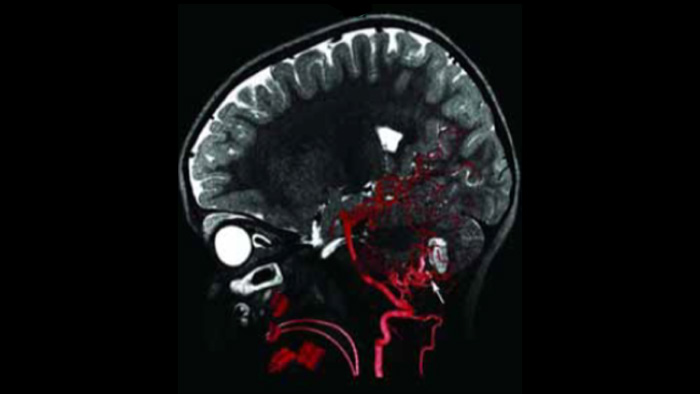

O MR-CT Roadmap oferece a possibilidade de sobrepor um exame de SmartCT Angio ou Angio de RM previamente adquirido com fluoroscopia em tempo real para visualizar os limites da lesão e a vascularização correspondente para avaliação de risco. A reutilização de dados pré-adquiridos ajuda-o a gerir a dose de raios X e o meio de contraste.

Utilize a imagiologia de SmartCT Soft Tissue no conjunto Neurovascular para verificar o sucesso do tratamento e identificar hemorragias.